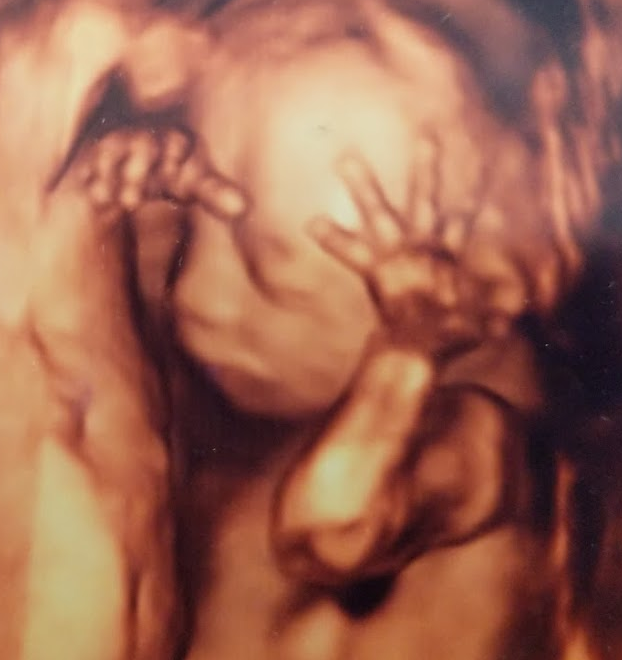

20-22 week Ultrasound . The detailed mid trimester scan is the single most important scan in pregnancy . This is the optimal time to detect fetal abnormality . Other issues such as placental site and growth will also be assessed . Generally, views of the baby are excellent and this scan is enjoyed enormously by parents .